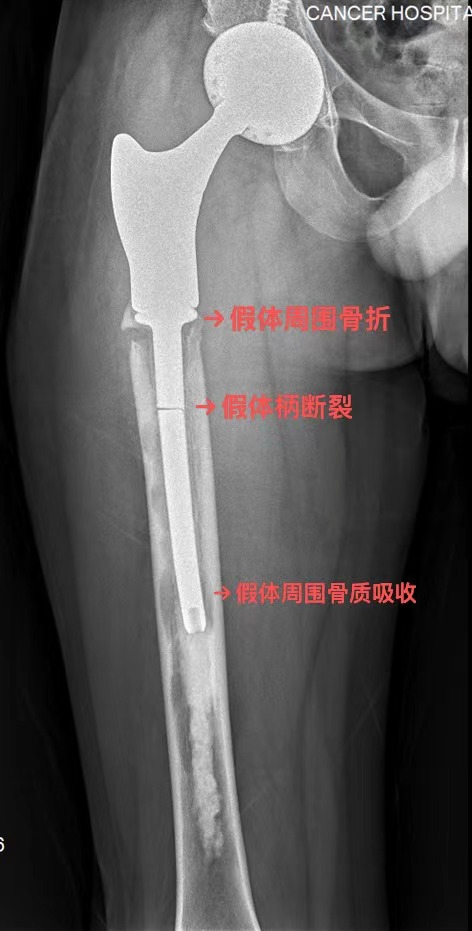

然而命运多舛,半年前他因为假体松动在外院进行了右人工股骨头翻修术,仅仅过了几个月,他再次感觉行走不稳,完善检查后发现再次出现假体松动并且假体柄断裂。转诊多家医院后,此次他决定到我院骨科门诊就诊。

▶ 因患者此前进行过多次髋关节手术,局部解剖结构因瘢痕修复而改变,手术入路解剖标志不清晰,骨质条件差。

▶ 手术目标在于完整取出嵌入髓腔的断裂假体柄及其附着的骨水泥,并重新植入、妥善固定新假体,难度远高于一般的髋关节置换手术。